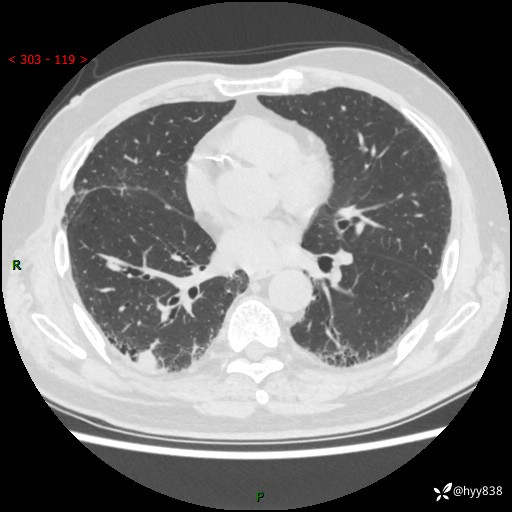

71岁/男,咳嗽伴气促半月。一年前肺手术史,又见两个结节,穿刺结果意外---结果公布~

【现病史】:患者半月前无明显诱因出现咳嗽、咳痰,为白色粘痰,无明显加重与缓解因素,伴气促,无发热,无大量脓痰,无胸痛、咯血,无哮鸣音,到我院就诊,胸部CT示右肺结节增大,并口服药物治疗无明显好转,具体用药不详,为求进一步治疗随来我院,经门诊以“孤立性肺结节”收入我科。 病程中患者精神、饮食可,睡眠不佳,大小便正常,体力下降,体重未见明显下降。

[既往史]:2022-06于当地第一人民医院确诊慢阻肺,现规律使用杰润(1次/日);2023-04-06于当地市第一人民医院行胸腔镜右肺上叶楔形切除术+右肺上叶切除术+淋巴结清扫术+胸膜黏连松解术,确诊为右肺鳞癌 pT2aN0M0 Ib期

【检查】:胸部CT平扫+增强